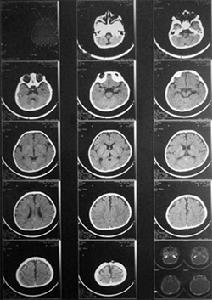

(5)皮質盲頭顱CT可顯示枕葉皮質軟化灶,急性球後視神經炎頭顱CT正常。